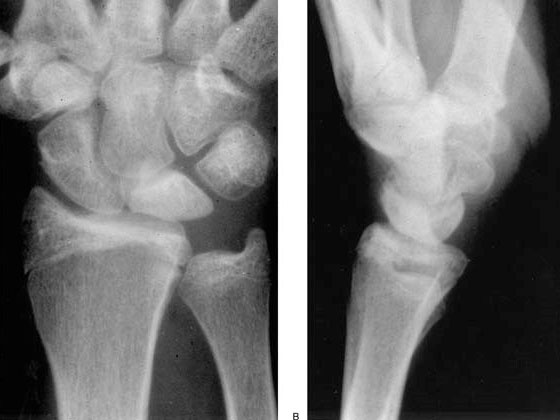

Alteraciones mecánicas o anatómicas, como una discrepancia en la longitud de los huesos: tener un cúbito corto (figuras 1 y 2) y una determinada forma anatómica de semilunar (tipo I) (figura 3).

Figuras 1 y 2: cúbito minus o corto (predisponente de Kienböck)

Figura 3: tipos de formas del semilunar. Mayor riesgo el tipo I con cúbito corto